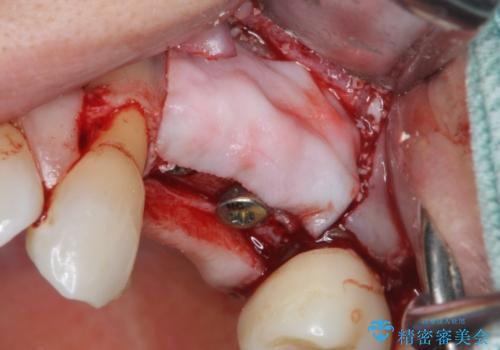

歯の穿孔(内部穴が開いている状態)破折等、歯を保存することができない問題が小臼歯には認められたので抜去を行います。

抜去後の補綴治療は長いブリッジではなくインプラント治療を希望されましたが、穿孔・破折による周囲の骨吸収をリカバリーすべく骨の造成を伴うインプラント治療を計画します。

インプラント治療を行うにはインプラント周囲に十分な骨の幅・高さが必要です。

今回はが原因で失われてしまった骨の幅を回復することで長期的な予後を見込めるインプラント治療を行うことができました。